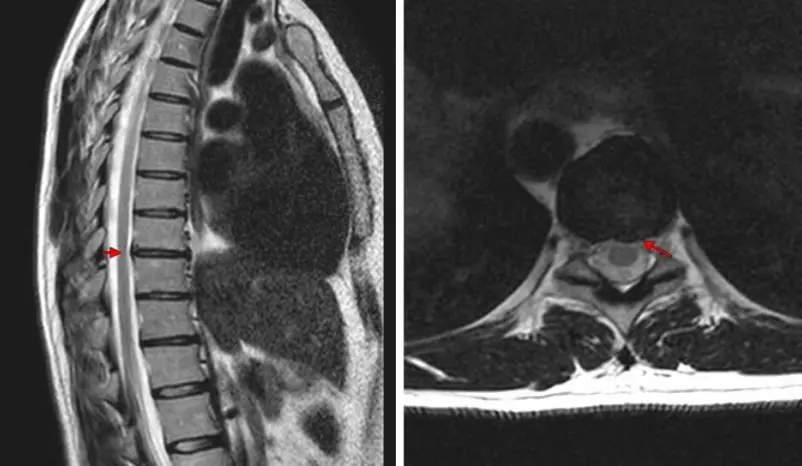

EKG iliyoonyesha kuwa moyo wangu uko sawa. Hospitalini nilifanyiwa uchunguzi kamili na nikagundua kuwa mimi nina osteokondrozi ya kifua. Sikuwa nikitazamia hili! Nafanya mazoezi, naenda kwenye yoga na nalala kwenye godoro la ortopediki. Yote hayo bure...